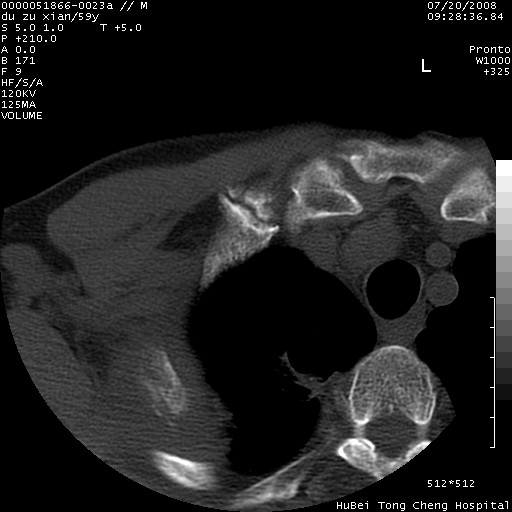

以下是引用宇宙ct在2008-8-25 23:21:00的发言:[br]右肺周围性肺癌并肋骨转移,纵隔淋巴结转移。

以下是引用zsl6918在2008-8-25 22:40:00的发言:[br]右肺周围性肺癌并肋骨转移,纵隔淋巴结转移。

以下是引用zy_zj在2008-8-26 15:24:00的发言:[br]单从病变本身,我倾向良性炎性病变,但肋骨转移了,所以说是考虑右肺周围性肺癌并肋骨、纵隔淋巴结转移可能性大。